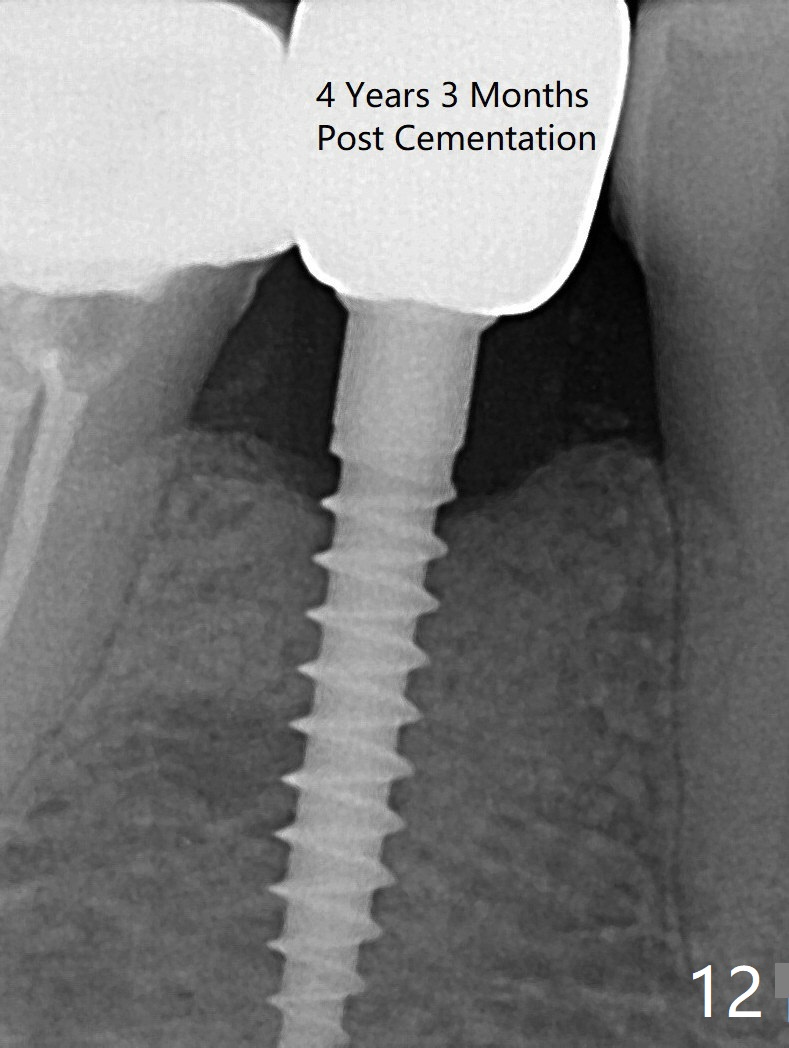

Preop photo shows the distal inclination of the tooth #28 (Fig.1).  The distal surface of the latter is reduced before incision for implant placement at #29 (Fig.2).  The buccolingual width is approximately 4 mm, as compared to 3 mm implant positioner (Fig.3).  After 1.2x10 mm osteotomy (Fig.5), the mesiodistal cortical bone is removed with a small high-speed fissural bur (Fig.4).  When a 2.5x12(2) mm 1-piece implant is placed (Fig.6), there is no buccal (Fig.7) or lingual plate perforation.  There is no postop paresthesia.  There is mild bone loss distal 4 months postop (Fig.8 *).  Take photos before and after permanent crown cementation to show increase in ridge width after bone graft and improvement in gingival health after provisional modification.  Take PA and/or BW post cementation to show that the distal bone resorption (Fig.8 *) is partially due to angulation.  No continuous bone loss 15 months post cementation (Fig.9).  There is mild bone resorption mesially 2 years 3 months post cementation (Fig.10).  The soft and hard tissues remain healthy 4 years 3 months post cementation (Fig.11,12).